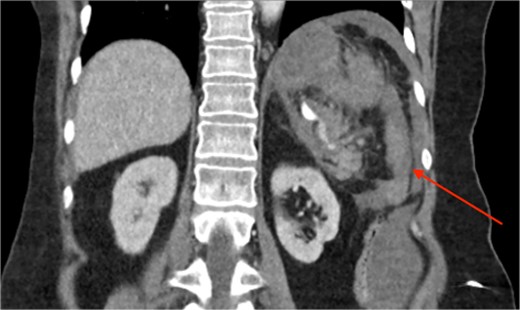

Triple-phase computed tomography (CT) of the abdomen and pelvis revealed a sizeable acute haematoma in the left upper abdomen, below the gastric fundus and body, alongside the pancreatic tail and splenic hilum, extending amongst the proximal small bowel mesentery and into the left subphrenic space. The origin of the haemorrhage appeared to arise from the left upper quadrant. There was a pseudoaneurysm in close proximity to the pancreatic tail and splenic hilum, apparently arising from the adjacent distal splenic artery. CT scan did show local contrast extravasation into the haematoma, as mentioned above (Figs 1–3).

CT of the abdomen and pelvis, coronal plane, arterial phase. Contrast extravasation from the ruptured SAP.